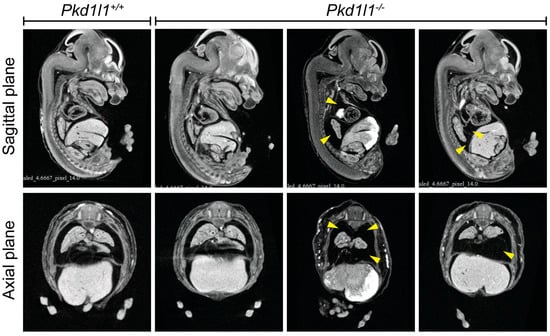

3.7. Observation of Pleural Effusion in Pkd1l1−/− Embryos